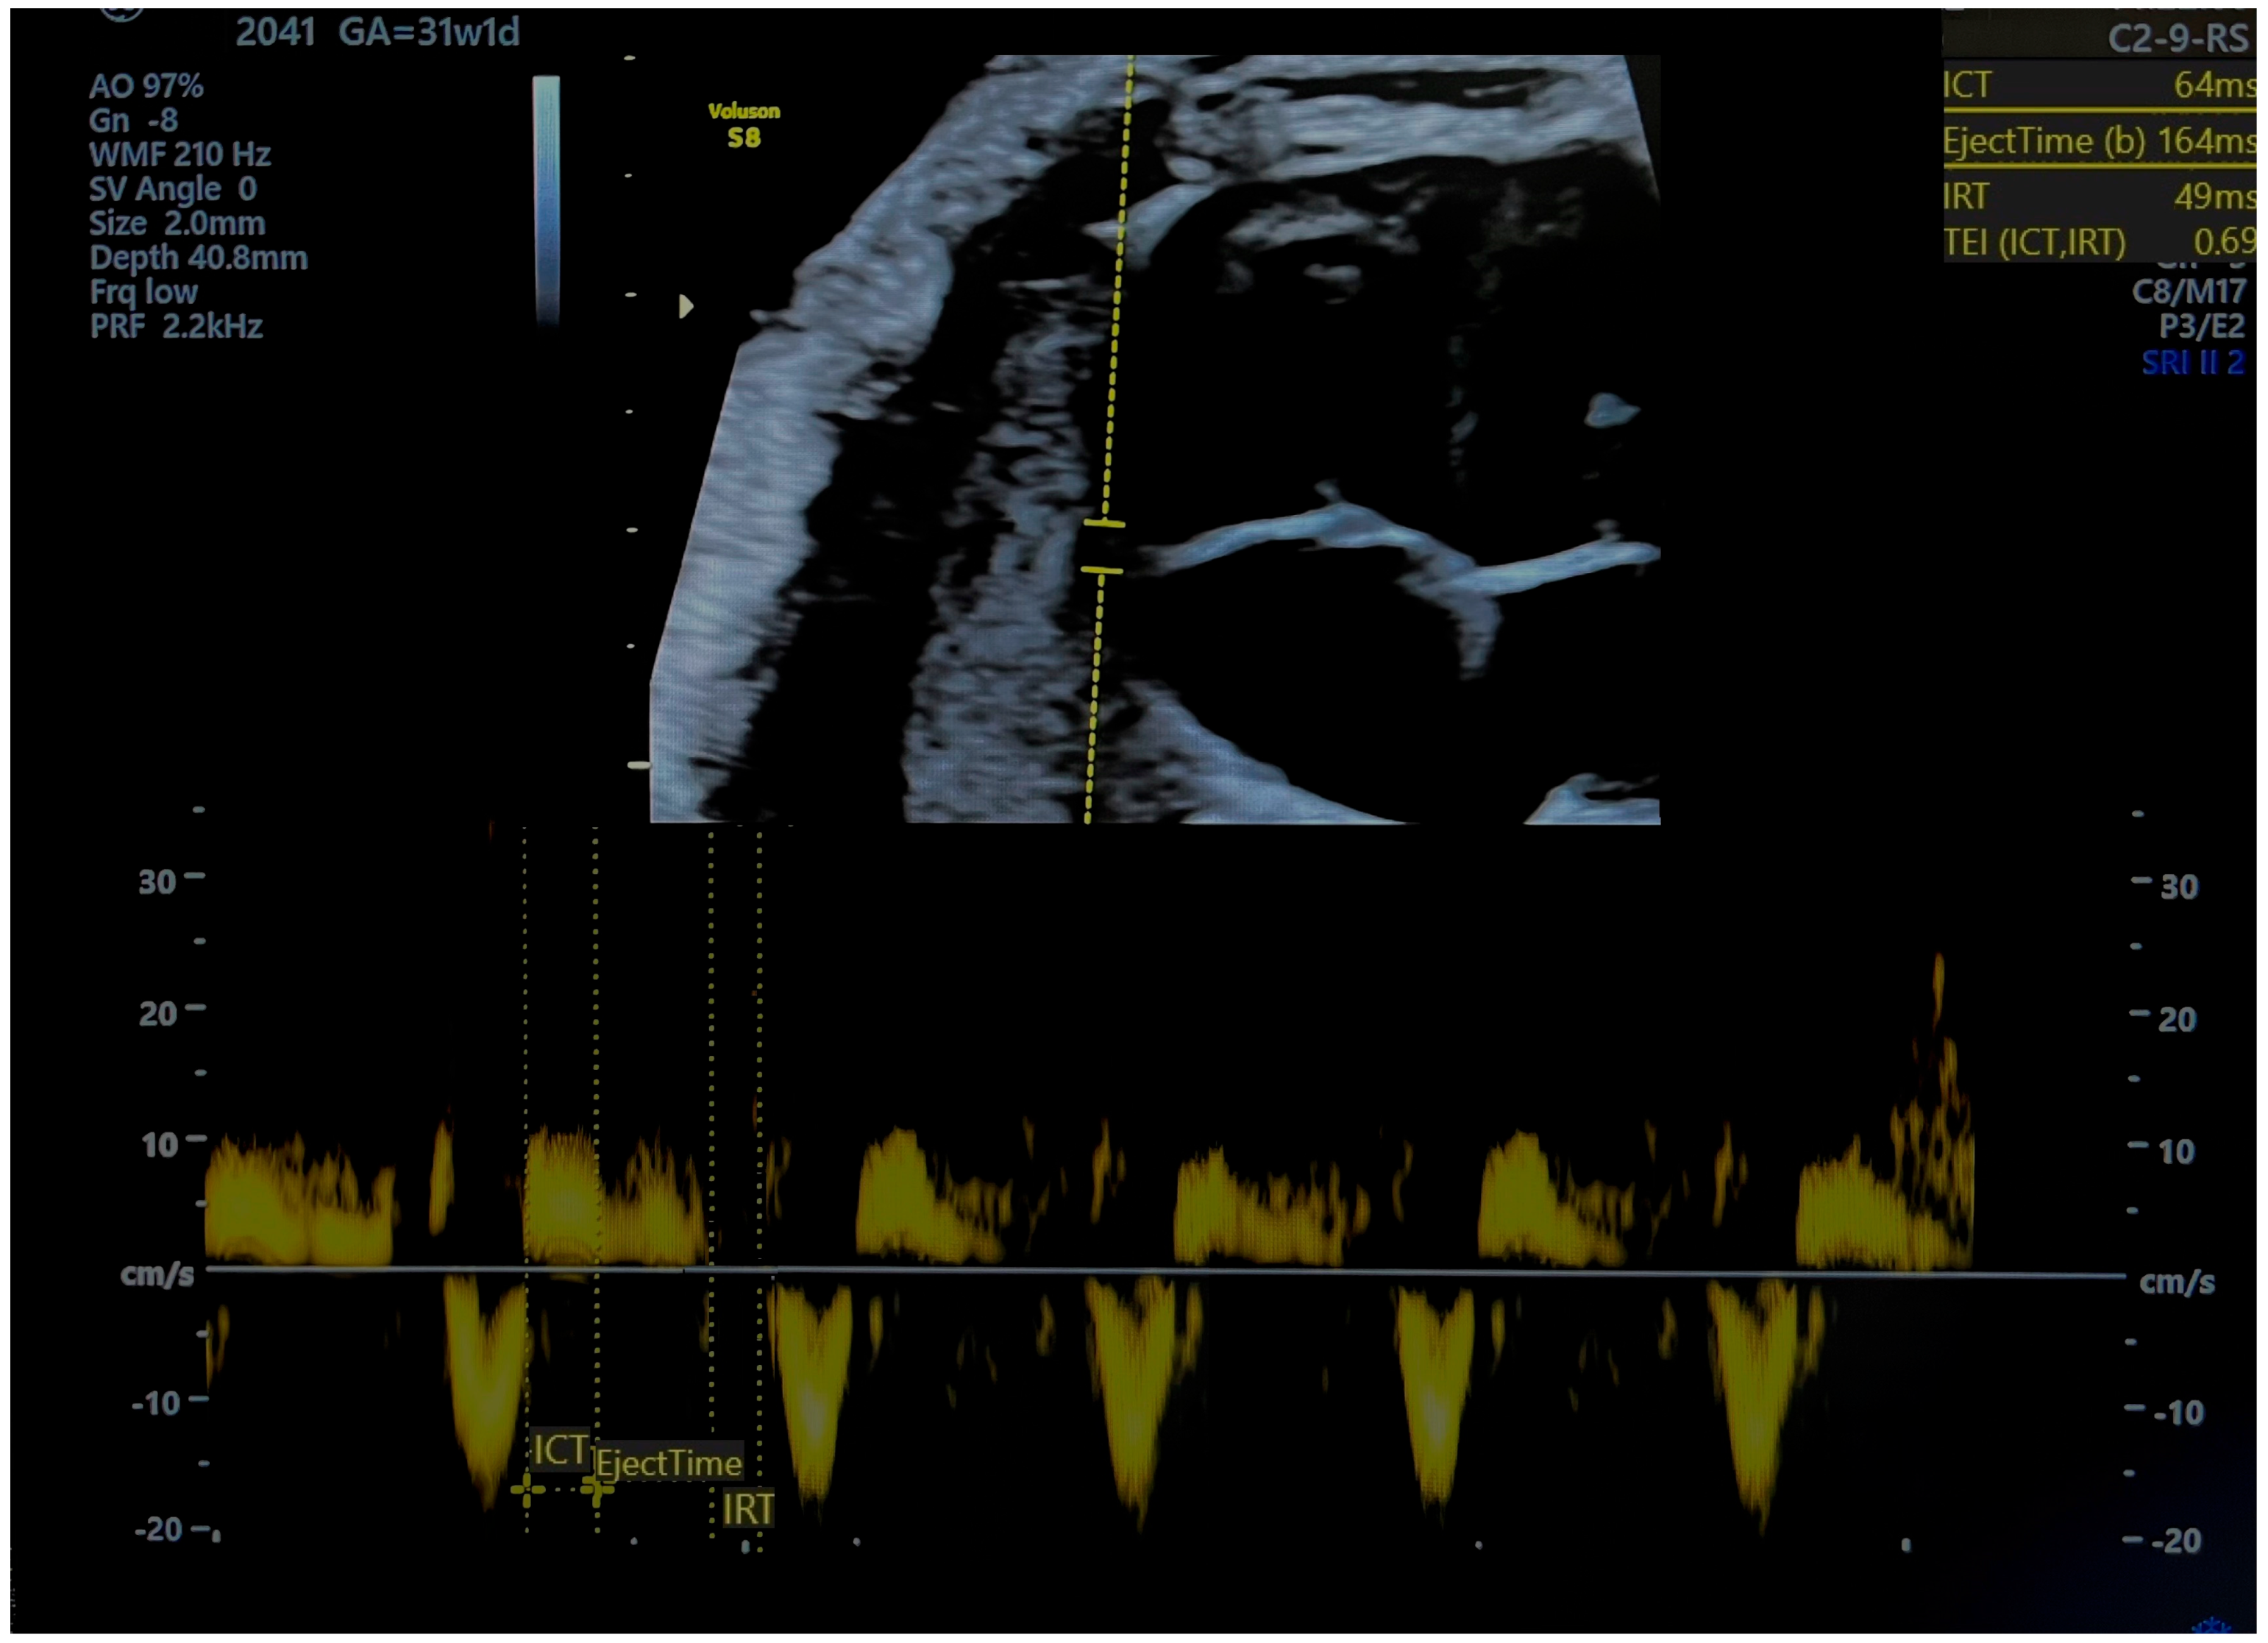

| RMPI TDI Values: Average 0.36 (0.28–0.44). Normal RMPI cut-off: 0.47 and below. | RMPI TDI Values:

| Timing: MPI alters before AoI and DV by 26, 12, and 5 days before delivery, respectively, which means that diastolic dysfunction occur prior to hypoxia. | Timing: MPI becomes altered before AoI and DV flow, which means that diastolic dysfunction occurs prior to hypoxia. |

| Cardiac Impairment:

| Predictive Value: A proportion of fetuses classified as SGA have increased MPI values; therefore, these fetuses may suffer true growth restriction, and the MPI becomes altered before changes in the blood flow reach cut-off values for FGR. |